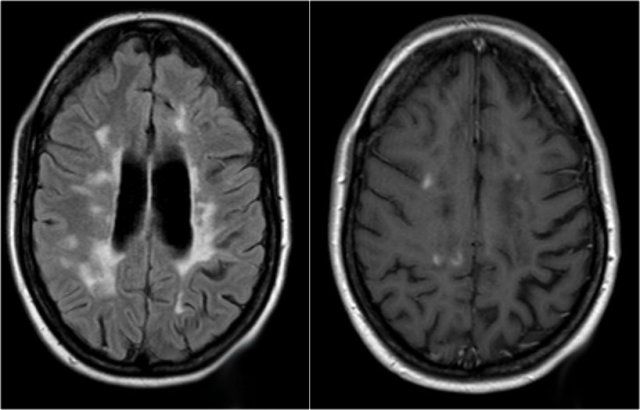

The MRI of the brain shows periventricular lesions and a lesion in the corpus callosum.

These locations are very specific for MS.

In another patient there are non-specific lesions in the cord.

Based on the examination of the spine alone, we have a broad differential diagnosis.

However when we examine the brain, it becomes obvious that we are dealing with MS.

In this case the findings in the brain are very helpful.

The location of the lesions is very typical: pons, periventricular and subcortical.

The images show abnormal signal around the third and frontal horns of the lateral ventricles.